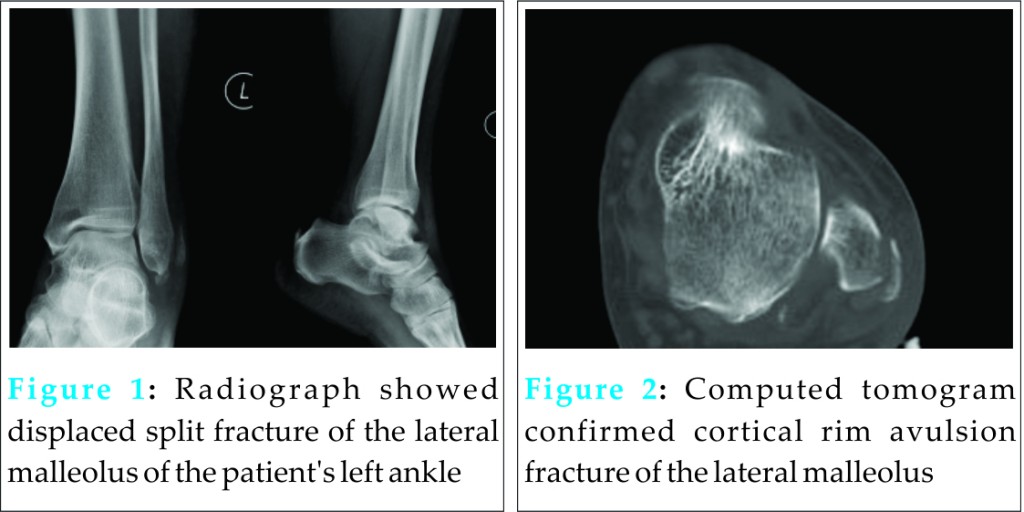

There was local tenderness at the posterolateral ankle. Radiograph showed displaced split fracture of the lateral malleolus (Fig 1).

The operated ankle was protected in a short leg cast and non-weight bearing for 4 weeks. Clinically, the peroneal tendons were located in the retromalleolar groove and no subluxation of the tendons was detected. Radiographs taken 2 months after the operation showed radiolucency at the lateral malleolus and the fracture still not healed (Fig 4).